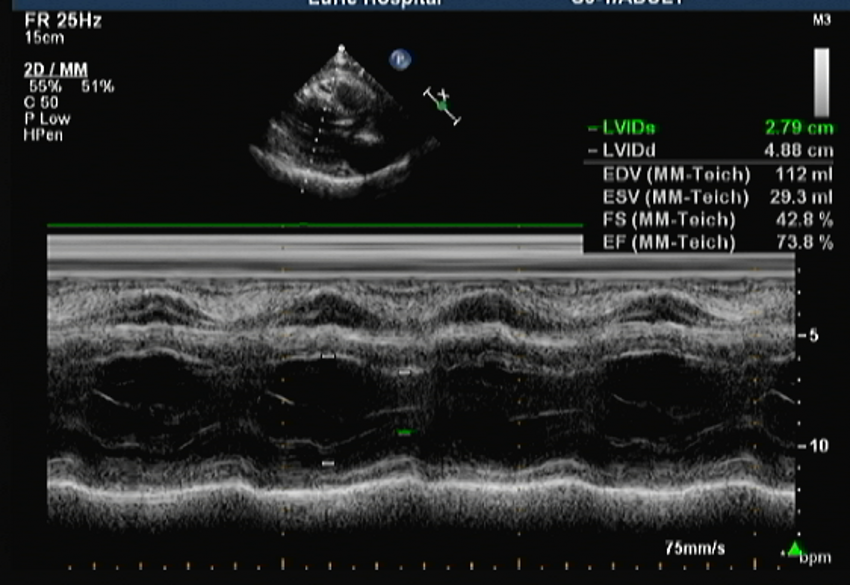

心脏超声

根据心电图、冠脉造影结果,考虑急性下壁、后壁心肌梗死 冠状动脉粥样硬化性心脏病 心功能KILLIP I级诊断成立,已行介入治疗,开通梗死相关血管,术后无不适,继续给予冠心病二级预防治疗,完善心脏彩超明确心脏结构与功能改变,密观病情。